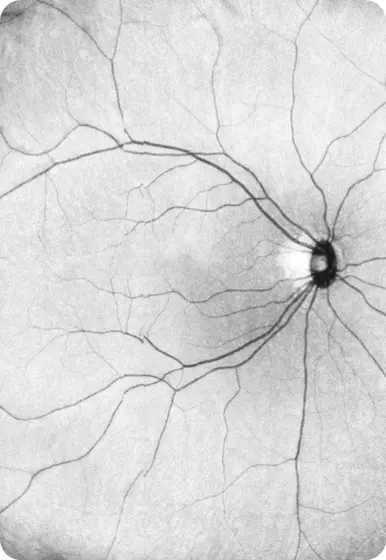

iCam™

Our patented Scanning Laser Ophthalmoscope (SLO) camera is designed to capture high-quality, truly ultra-wide field images of eyes across all ages.